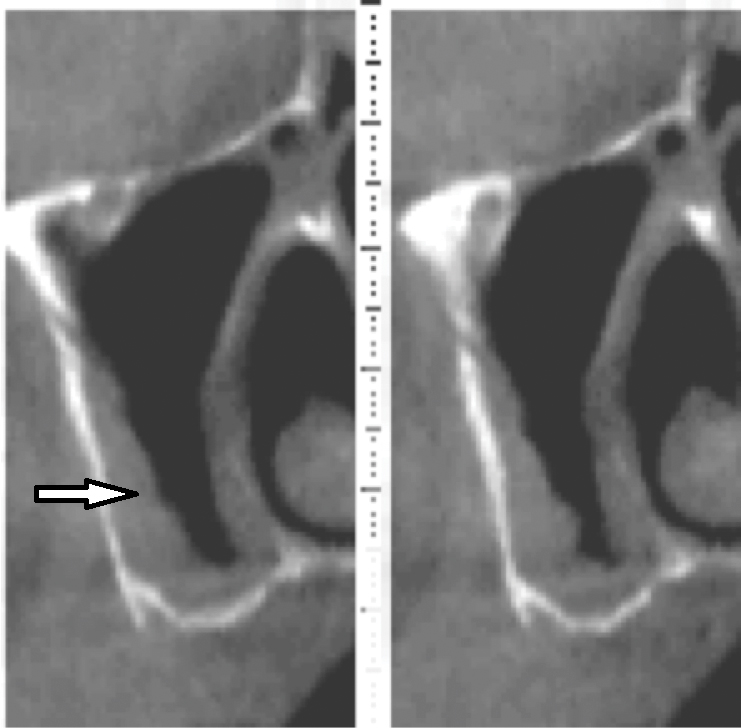

Submandibular Fossa and Mylohyoid Ridge

The submandibular fossa is denoted by an undercut in the posterior mandible (Figure 3). It is located beneath the mylohyoid muscle. This site must be intraorally palpated before implant placement because there may be an undercut in the mandibular molar area. In this regard, Parnia et al reported that 52% of patients manifest concavities 2 mm to 3 mm deep, and 28% of the examined regions demonstrated concavities of more than 3 mm.11 Thus, when there is a large undercut, caution must be exercised in order to avoid drilling into the floor of the mouth, which could sever a blood vessel and result in hemorrhaging. The ridge on the lingual aspect of the mandible depicted in Figure 3 is the mylohyoid ridge, which provides the origin of the mylohyoid muscle.

Fig 3. Submandibular fossa and mylohyoid ridge: cross-sectional view. A: The submandibular fossa may present a large depression in the mandible. B: The mylohyoid ridge provides the origin for the mylohyoid muscle.